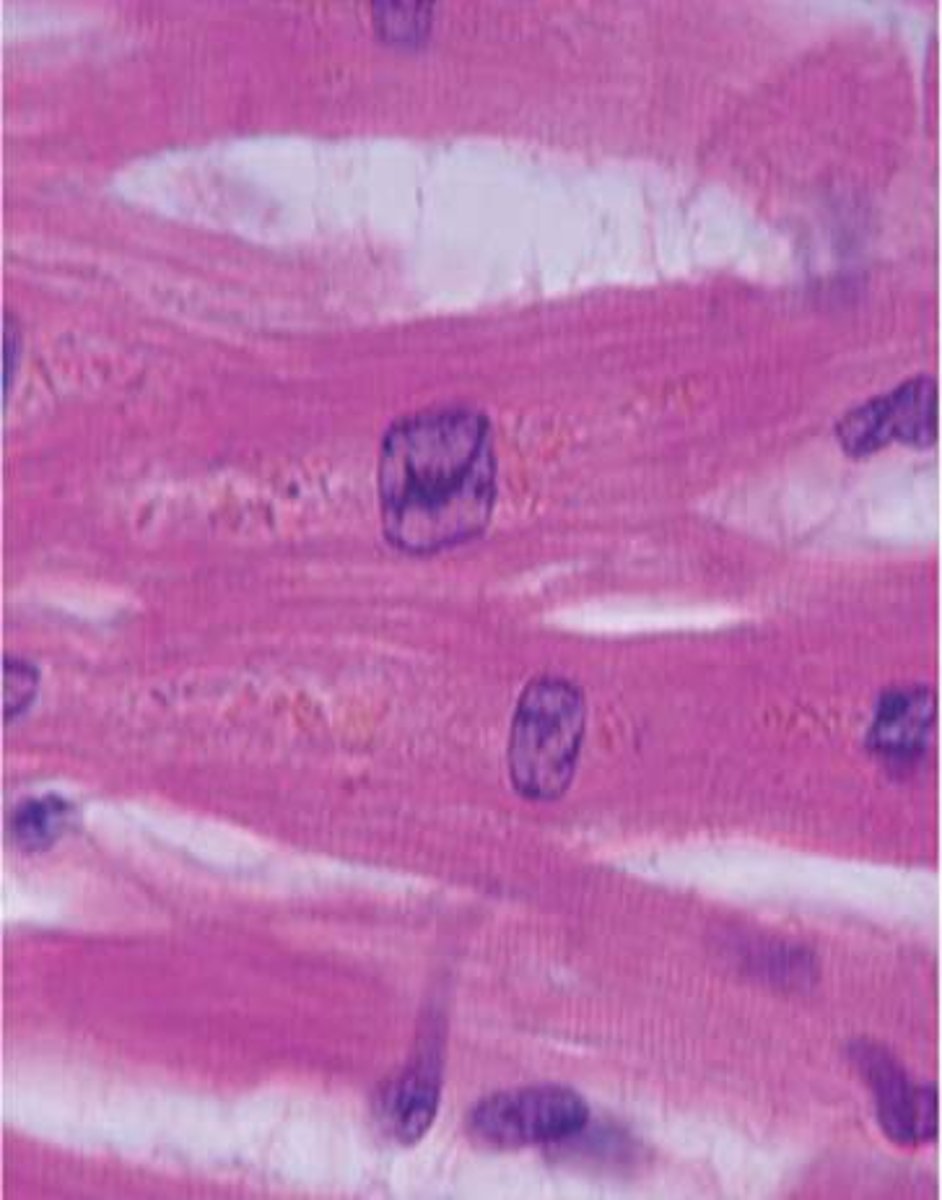

striation

what component of muscle tissue are the lines

myocyte

what component of muscle tissue is this

cardiomyocyte

intercalated discs

skeletal muscle

what type of tissue is this

cardiac muscle